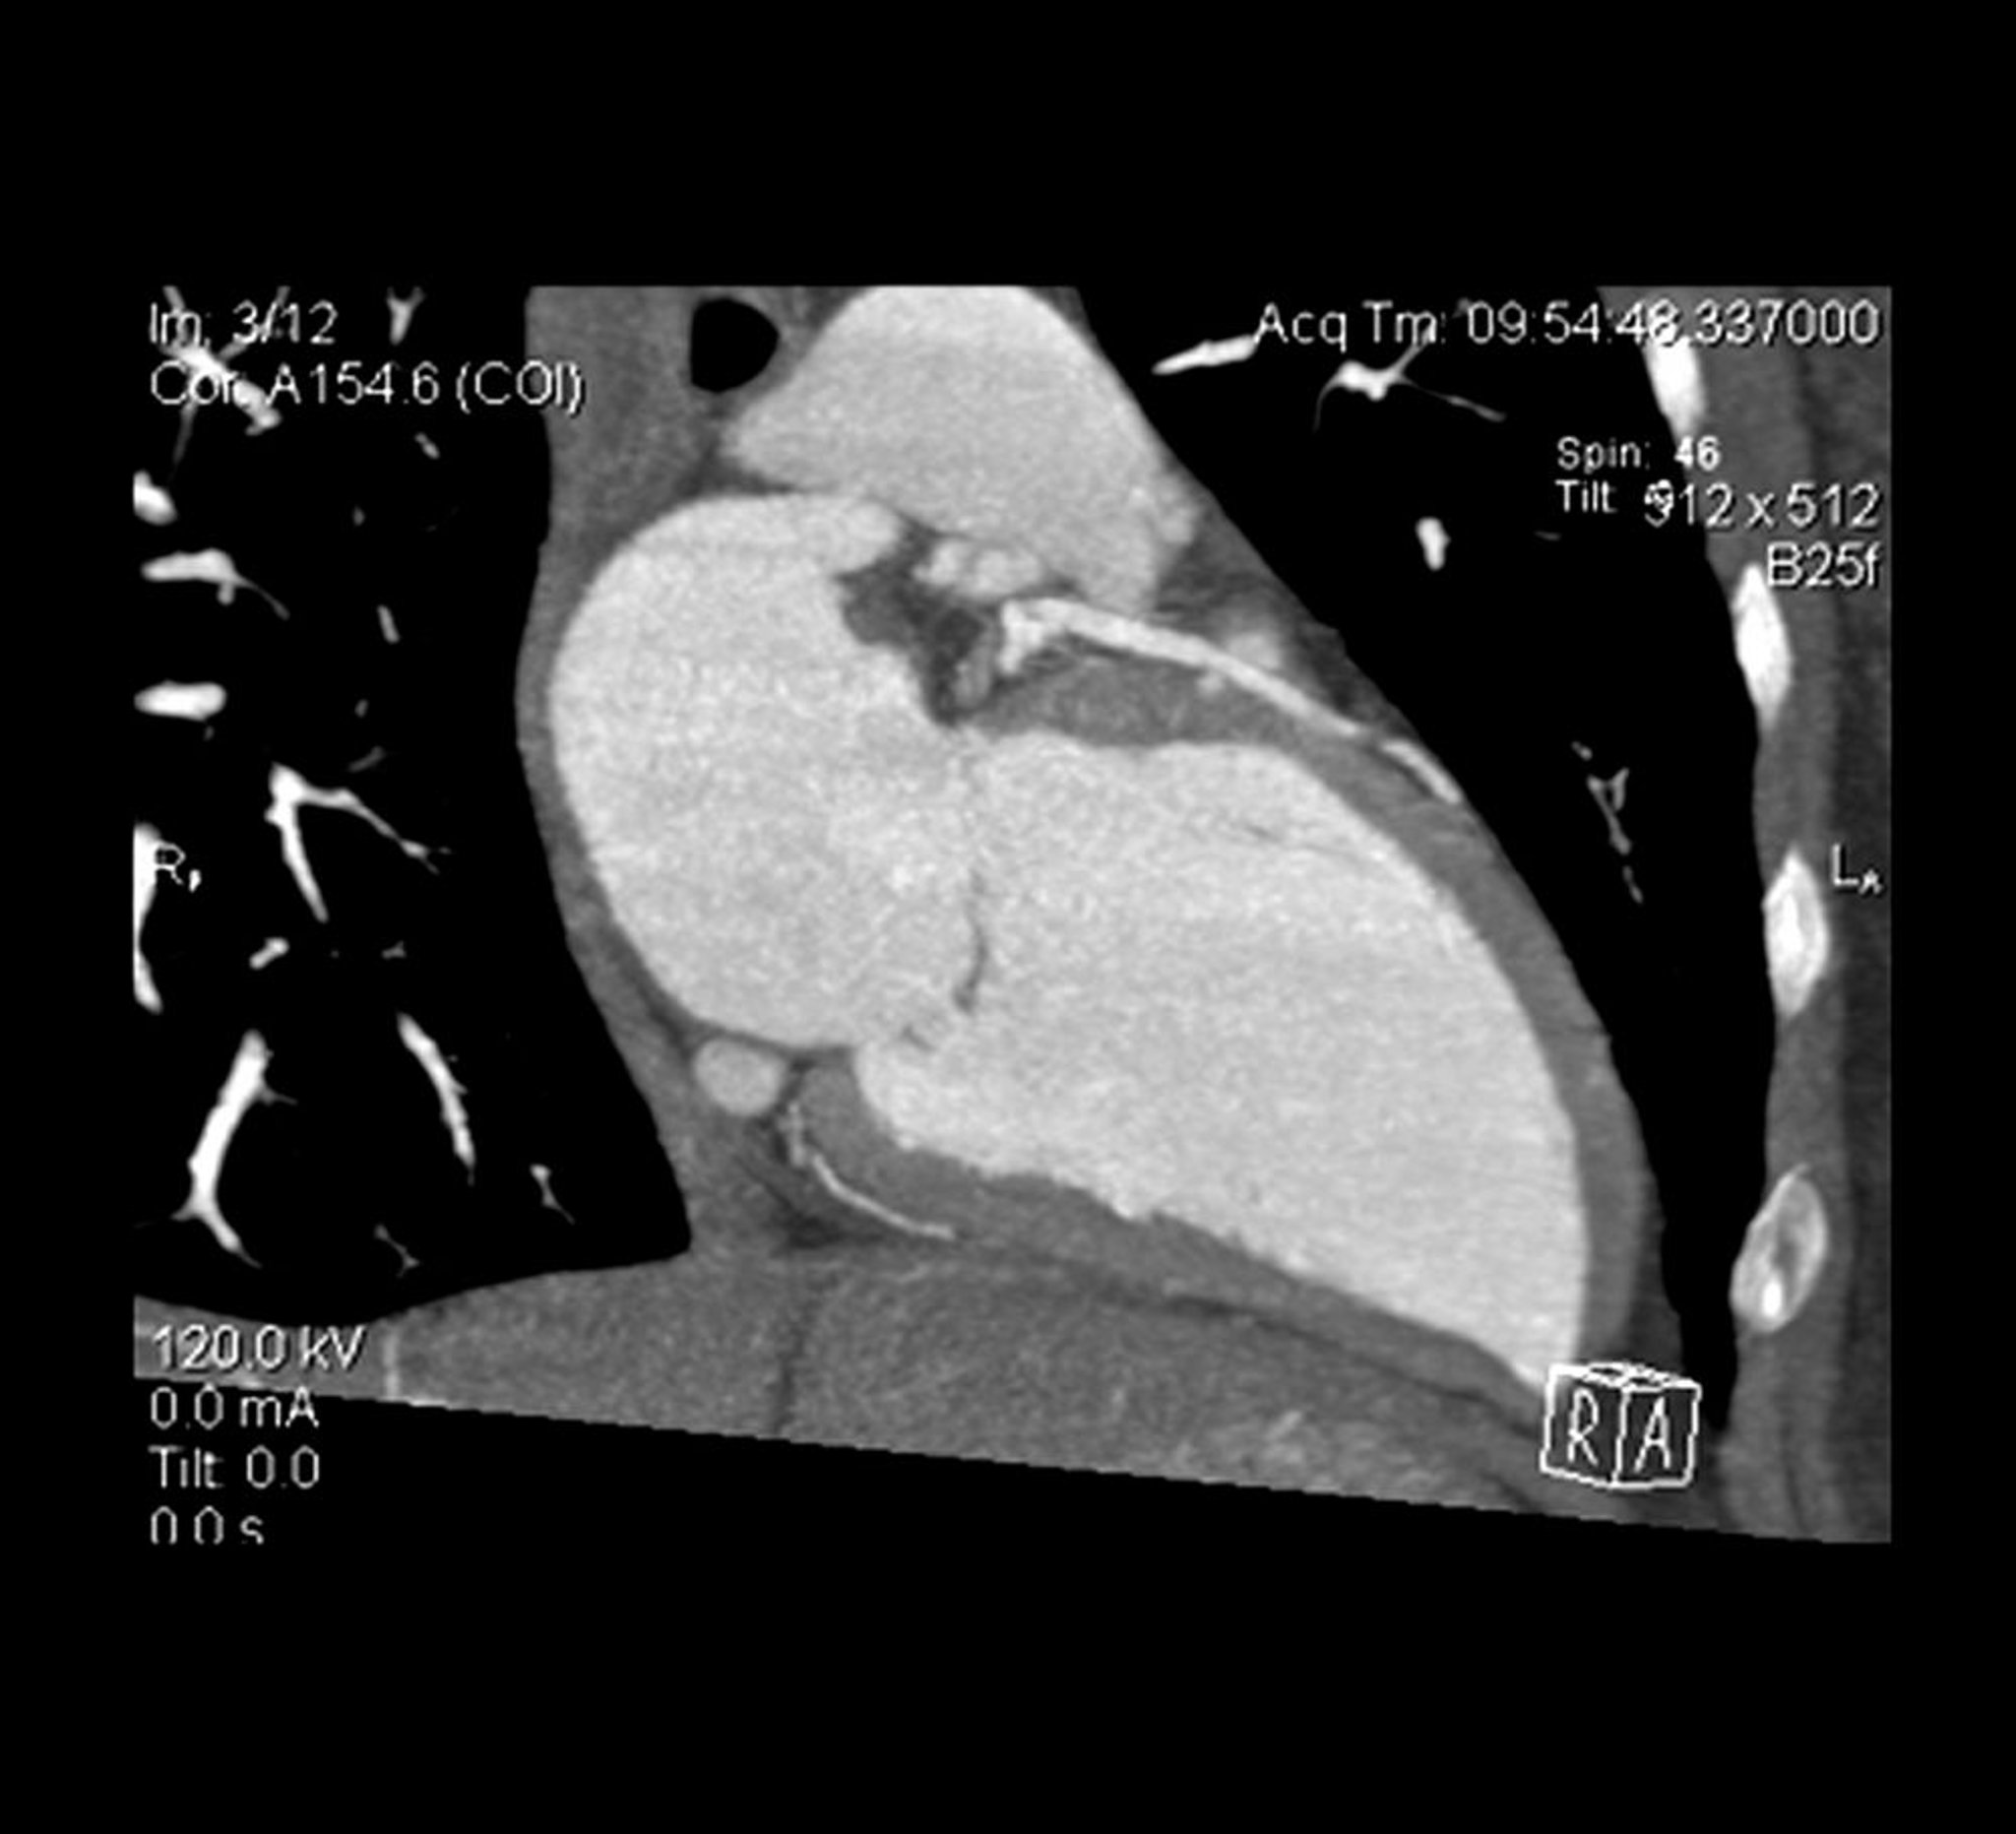

КТ-ангиограмма сердца

На поперечном срезе КТ-ангиограммы сердца показан левый желудочек и левая передняя нисходящая артерия.